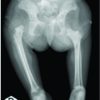

A 20-year-old male, an athlete who was preparing for a national level long jump competition fumbled and then landed awkwardly leading to varus and hyperextension injury to his left knee. He was unable to walk. The patient was immediately taken to a local hospital where his left lower limb was immobilized in a splint and a standard anterior posterior and lateral radiograph and MRI is shown in Fig. 1.

He was referred to our center for further management. On examination, there was fullness in the supra-, para-, and infrapatellar pouch. Tenderness was present over the lateral condyle of the left tibia and the lateral and posterolateral joint line was also tender. Active knee range of motion (ROM) was 10–30°. Passive knee ROM flexion and extension were possible from 0 to 90° as compared to ROM of 0–140° of the unaffected knee. Grade III Lachman’s test. Significant laxity (3+) was seen on a varus stress test at various degrees of flexion. There was a complete loss of ankle and toe dorsiflexion. Muscle testing of dorsiflexion of ankle including tibialis anterior, extensor digitorum, and extensor hallucis longus was suggestive of a complete foot drop. X-ray of the knee revealed a Segonds Fracture (Avulsion fracture of lateral condyle of the tibia). Magnetic resonance imaging (MRI) was suggestive of a complete tear of ACL, complete tear of the PCL, PLC injury including LCL avulsion, biceps femoris rupture, and Segonds fracture of the left tibia. Nerve conduction velocity study showed CPN palsy. A two-staged procedure was planned. The Stage I of the surgery was performed on day 2 of the admission. In Stage 1, the patient was examined under anesthesia. Anterior drawer test and posterior drawer test positive, varus stress test positive at 0 and 30°. Dial test was positive at 0 and 90°. Pivot shift test was found to be positive. Initially, diagnostic arthroscopy was done which showed – complete ACL tear, complete midsubstance PCL tear, lateral meniscus tear, and lateral capsular rupture. The lateral meniscus was balanced and remnants of ACL and PCL were debrided to prepare for the next step. PLC was repaired with an open lateral approach. LCL was seen to be avulsed, iliotibial band and biceps femoris were seen to be torn, and large rent was seen in a lateral capsule. The common peroneal nerve was explored along its course and contusion of the nerve was observed at the anatomical part traversing on the posterior aspect of the fibula. The LCL was repaired using an interference screw. Segonds fracture was reduced using suture anchors. The rest of the PLC was repaired using double row style anchor insertion with ethibond and cannulated cancellous screw. Surgical neurolysis of CPN was performed 5 cm proximal and distal to the site of contusion. Post-operative radiograph of the patient after Stage 1 Fig. 2.